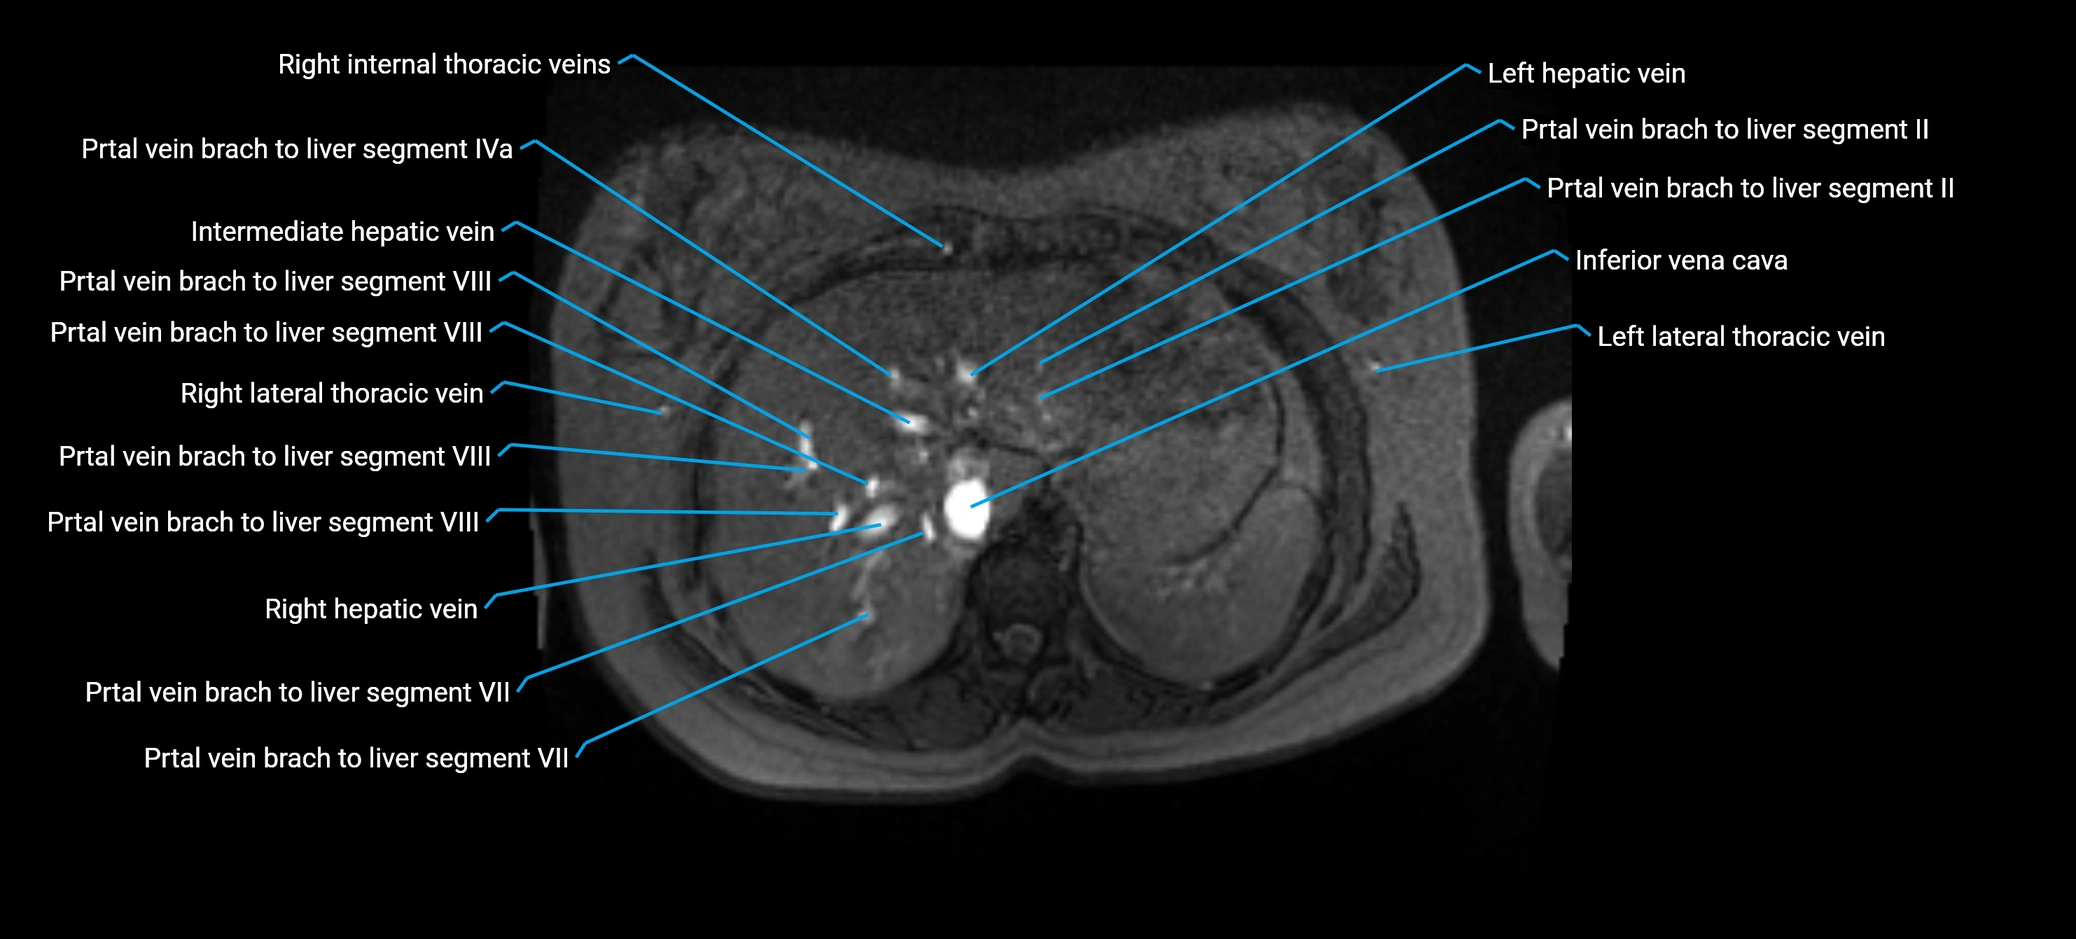

The anterior right branch of the portal vein is a major intrahepatic division of the right portal vein. After the main portal vein bifurcates into right and left branches, the right portal vein divides into anterior and posterior segmental branches.

The anterior right branch supplies the anterolateral liver segments (Segment V) and anteromedial liver segments (Segment VIII) within the right hepatic lobe. It operates as a key vascular route delivering nutrient-rich portal venous blood to the central and superior right liver.

MRI image

image